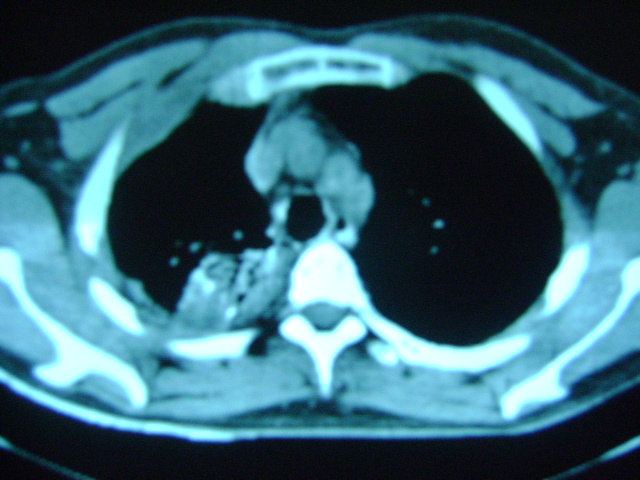

标题: CT16197:新手求教,M,42y,外伤入院,略感气紧,余无不适 [打印本页]

标题: CT16197:新手求教,M,42y,外伤入院,略感气紧,余无不适

肋骨骨折,肺挫伤,胸腔积液,不张?

肋骨骨折,右肺挫裂伤,右侧胸腔积液,没有气胸很奇怪啊

肋骨骨折,肺挫伤,胸腔积液,左肺代偿性气肿.

肋骨骨折,肺挫伤,胸腔积血.

右侧肋骨骨折,右肺挫伤,右侧胸腔积液(血)。

肋骨骨折,肺挫伤,双侧胸腔积血.

右上肺后段片状实变影有点状钙化,左下肺亦可见结节影,应考虑结核